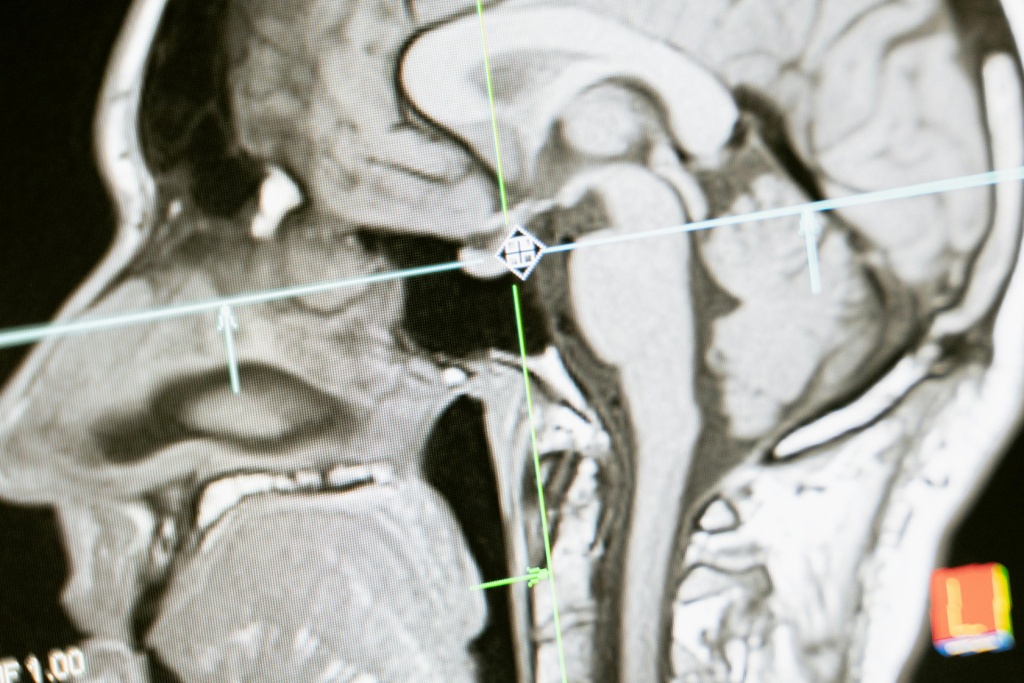

Предположим, у пациента обнаружили подозрительные изменения в тканях мозга на рентгеновских снимках. Для более точной диагностики врач назначает ему МРТ. Благодаря пониманию режимов МРТ, радиолог способен выбрать оптимальные параметры сканирования, что позволит получить высококачественные изображения мозговых структур с высоким разрешением. Это поможет точно определить характер и стадию заболевания и разработать наиболее эффективный план лечения для пациента.

Основная функция фМРТ заключается в том, чтобы позволить исследователям изучать активность мозга в реальном времени, что позволяет понять, какие участки мозга активируются при выполнении различных задач и функций. Этот метод широко используется в исследованиях мозговой активности, когнитивных функций, психических расстройств и нейрологических заболеваний.

В клинической практике фМРТ часто применяется для диагностики и мониторинга состояний, связанных с функционированием мозга, таких как эпилепсия, инсульты, шизофрения, депрессия и дисфункции речи. Также он может быть использован для планирования хирургических вмешательств, например, для определения местоположения функционально важных областей мозга перед операцией.

Предположим, пациент страдает от эпилептических припадков, которые не поддаются лечению медикаментозными препаратами. Врач назначает ему фМРТ, чтобы определить местоположение и характер активации участков мозга, вызывающих припадки. После анализа результатов исследования врачи могут решить о возможности проведения хирургического вмешательства для удаления или облегчения доступа к проблематичным участкам мозга.